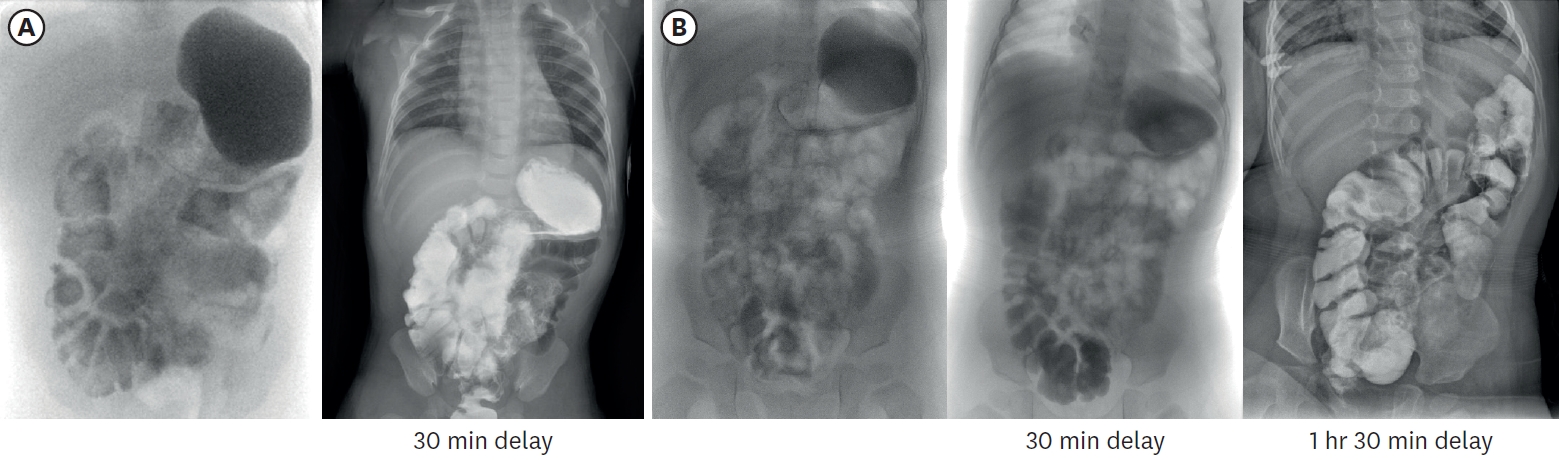

Stool output was carefully monitored, with diarrhea defined as output exceeding 20 g/kg/d. A notable increase in stool occurred primarily around month 4, when she started increasing enteral feeding, and during the beginning of weaning food. Initially, we adjusted to reduce the amount of feeding and increase TPN fluids to maintain hydration and nutritional supply. After starting weaning food, we tried to modify the ingredients and used various lactobacilli supplements with intermittent antidiarrheal drugs (Racecadotri, Hidrasec® Abbott Korrea, Seoul, Korea). She is currently maintaining a stable stool condition with a normal pattern, averaging 2 times per day and around 6 g/kg (Fig. 3). Through 20 months of follow-up, the patient demonstrated uncomplicated growth, so we gradually extended the outpatient visits and laboratory monitoring intervals from monthly to bimonthly. Last laboratory results taken at 20 months of age were all found to be normal, including liver function, albumin, heavy metals, and vitamins (Table 1). To monitor the bowel’s adaptation process, small bowel series examination was undertaken at 3 months and 16 months of age respectively (Fig. 6). It was noted that the IC valve transit time was increased more than twofold from 7 minutes to 14 minutes. This indicated an enhanced intestinal nutritional retention time, which resulted in improved nutrient absorption and overall intestinal function.

Fig. 6.

Small bowel series images taken at 3 months (A) and 16 months (B) of age respectively. In (A), contrast passage to rectum was observed after 30-minute delayed image, and total small bowel length was approximately 23.4 cm, including duodenum. In (B), contrast passage to ascending colon was observed after 30-minute delayed image, and total small bowel length was approximately 29.9 cm.

Fig. 6. Small bowel series images taken at 3 months (A) and 16 months (B) of age respectively. In (A), contrast passage to rectum was observed after 30-minute delayed image, and total small bowel length was approximately 23.4 cm, including duodenum. In (B), contrast passage to ascending colon was observed after 30-minute delayed image, and total small bowel length was approximately 29.9 cm.